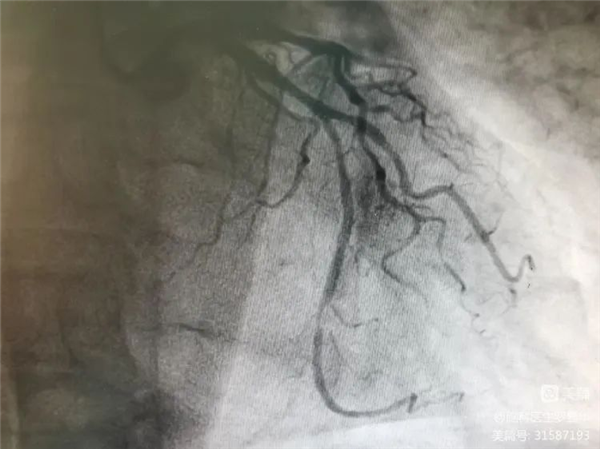

冠脈造影證實左旋支重度狹窄